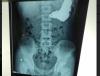

Tim dokter bedah RSUD Indramayu mengeluarkan puluhan paku dari perut seorang pria diduga ODGJ. (Foto: MPI)

Dia menuturkan, tim dokter kemudian melakukan rontgen terhadap pria tersebut. Dari hasil foto Rontgen itu diketahui ada banyak paku berukuran besar bersarang di dalam lambung korban.

Dari hasil Rontgen tersebut, Deden menyampaikan, terlihat ada benda asing di dalam tubuh pasien yang diduga adalah paku.

Salah satu dokter spesialis bedah yang menangani pasien tersebut langsung mengambil tindakan operasi selama dua jam. Dari hasil tindakan cepat itu, didapati sebanyak 70 batang paku yang sudah masuk ke dalam lambung si pasien.